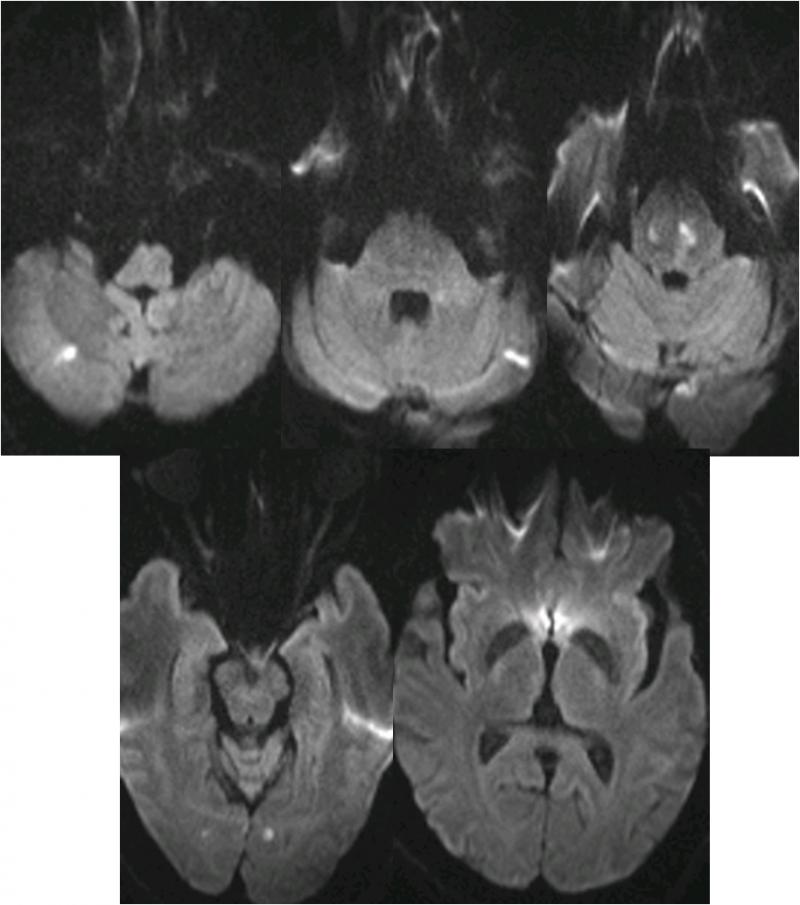

▼溶栓后MRI

▼于基底动脉远端及双侧大脑后动脉,分次给予阿替普酶共计5mg。

》12:10结束手术,带气管插管返回神经内科ICU。给予乌拉地尔持续泵入控制血压在110/70mmHg左右。

》20天后出院,NIHSS评分5分。